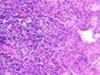

Doku ölümü. Hücrelerin ve dokuların ölmesi durumu.